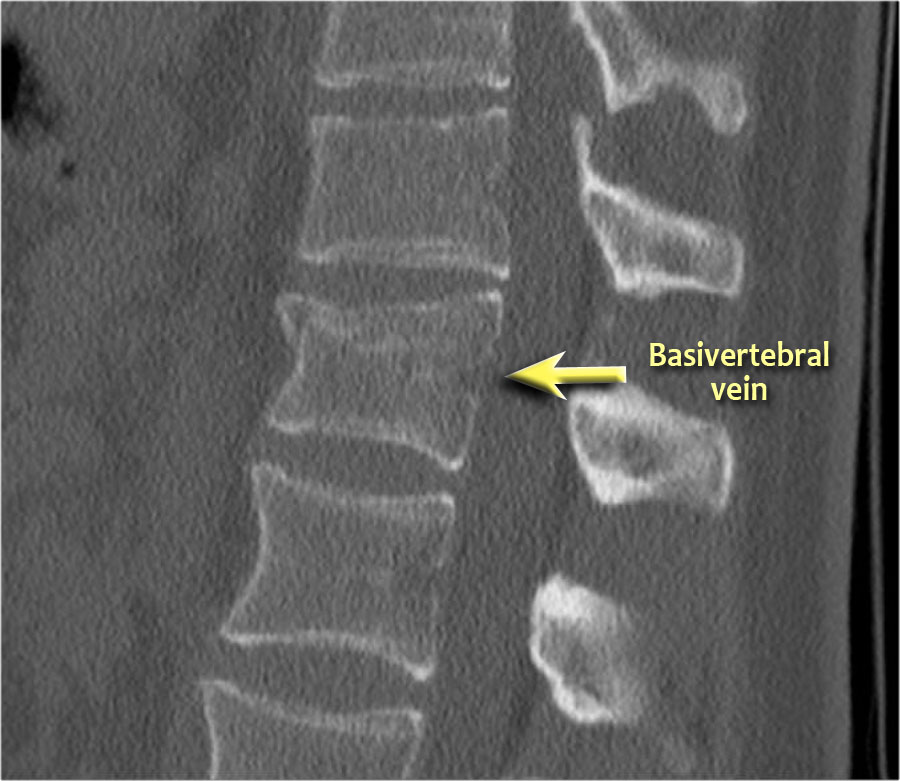

Các hình ảnh cho thấy một trường hợp gãy xương nén.

Dấu hiệu duy nhất quan sát được là sự gián đoạn vỏ xương ở thành trước trên của thân đốt sống và mất chiều cao nhẹ ở phía trước.

Vỏ xương phía sau thân đốt sống còn nguyên vẹn.

Hình tái tạo mặt phẳng đứng dọc cũng cho thấy sự gián đoạn vỏ xương.

Lưu ý rằng trên lát cắt axial dày 2,5mm, có thể bỏ sót các gãy xương này.

Cần xem xét các lát cắt mỏng để phát hiện những gãy xương tinh tế như vậy.